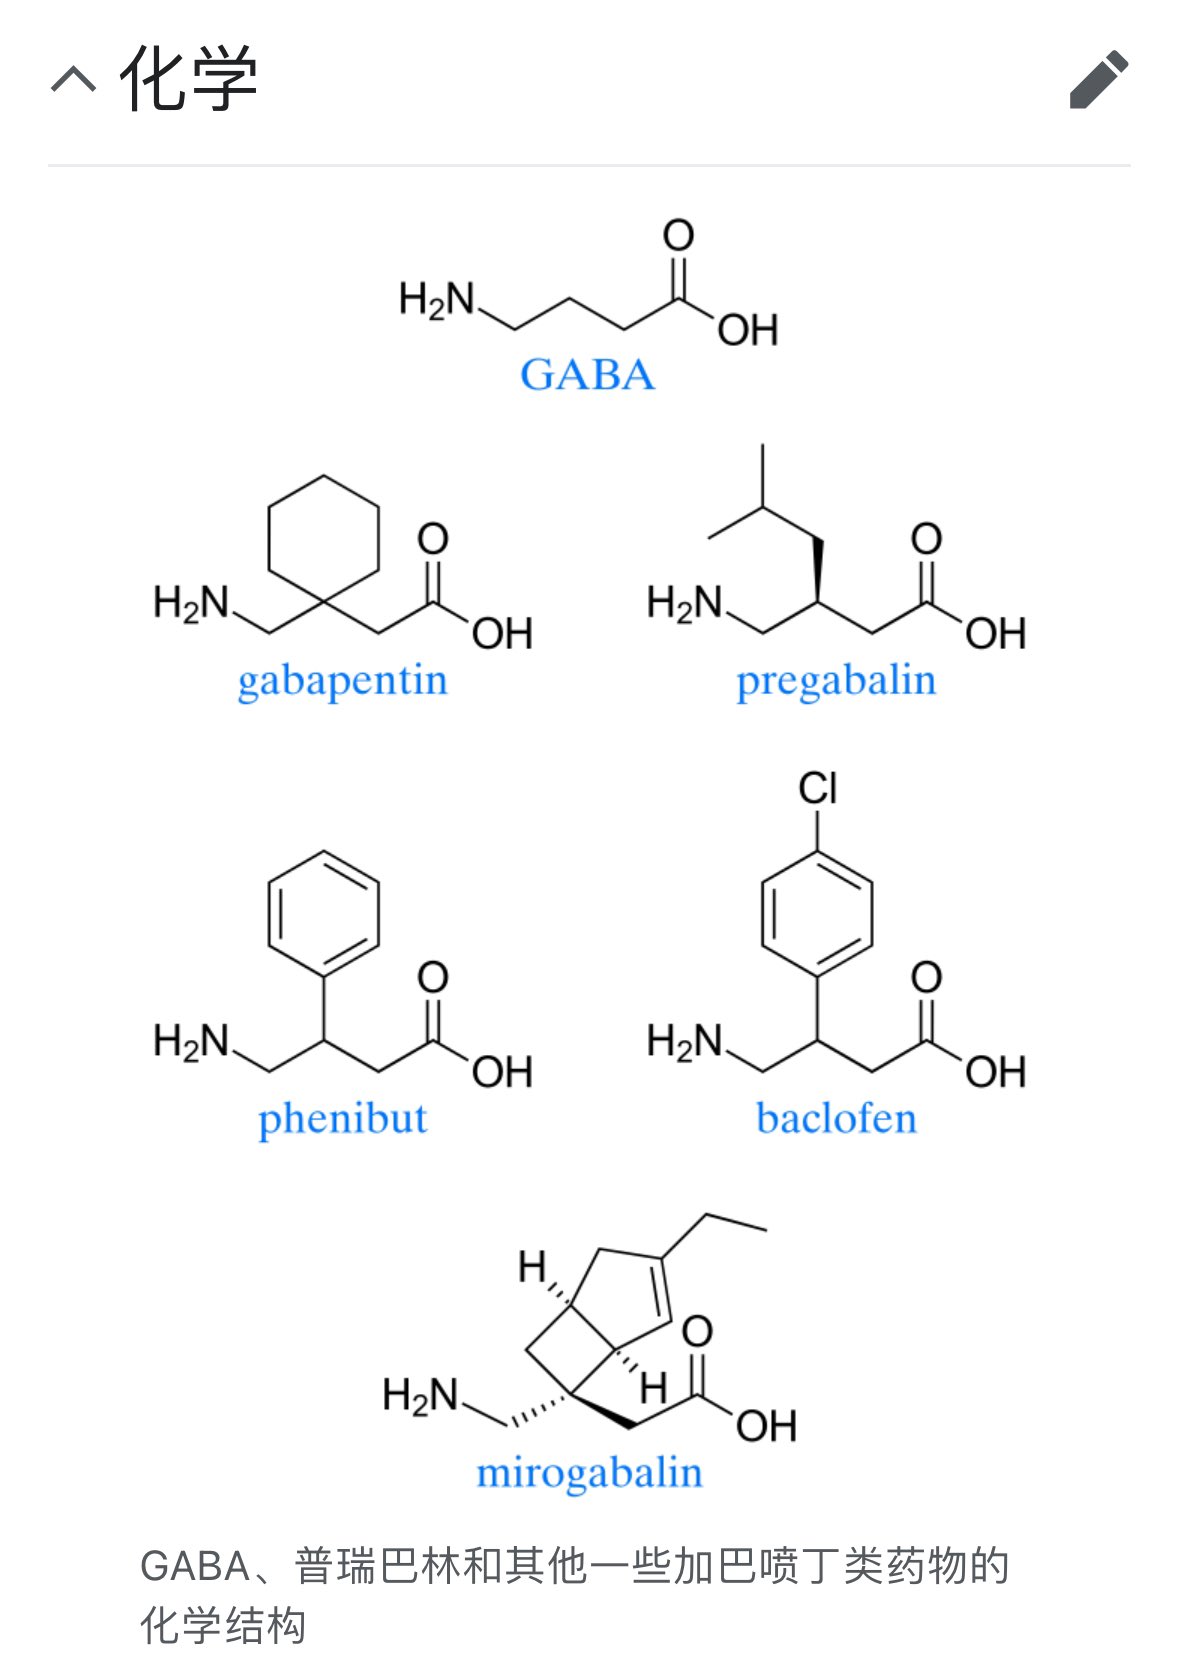

首先,从定义上讲,“反解离(anti-dissociative)”并不是一个标准的医学术语或者广泛认同的药理学分类。在正规资料,比如医学文献、维基百科、精神药理学教科书中,目前并没有“反解离药物”这个正式概念。

看上去像是为了描述某类特定效应而创造的术语(可能是nmda受体活性增强),用来对抗因NMDA受体拮抗剂(比如氯胺酮、DXM、PCP等)引发的解离体验(dissociation)。

那么更常见的是将其归入认知增强剂(cognitive enhancers),特别是改善认知连接性(connectivity)和现实感知(reality testing)的类型。

科学的处理方式一般是通过更细致的调节,比如微调NMDA/AMPA平衡、调节其他辅助途径(如GABA、5-HT、mGluR受体),而不是简单粗暴地用“NMDA增强剂”去顶回去。

科学的处理方式一般是通过更细致的调节,比如微调NMDA/AMPA平衡、调节其他辅助途径(如GABA、5-HT、mGluR受体),而不是简单粗暴地用“NMDA增强剂”去顶回去。